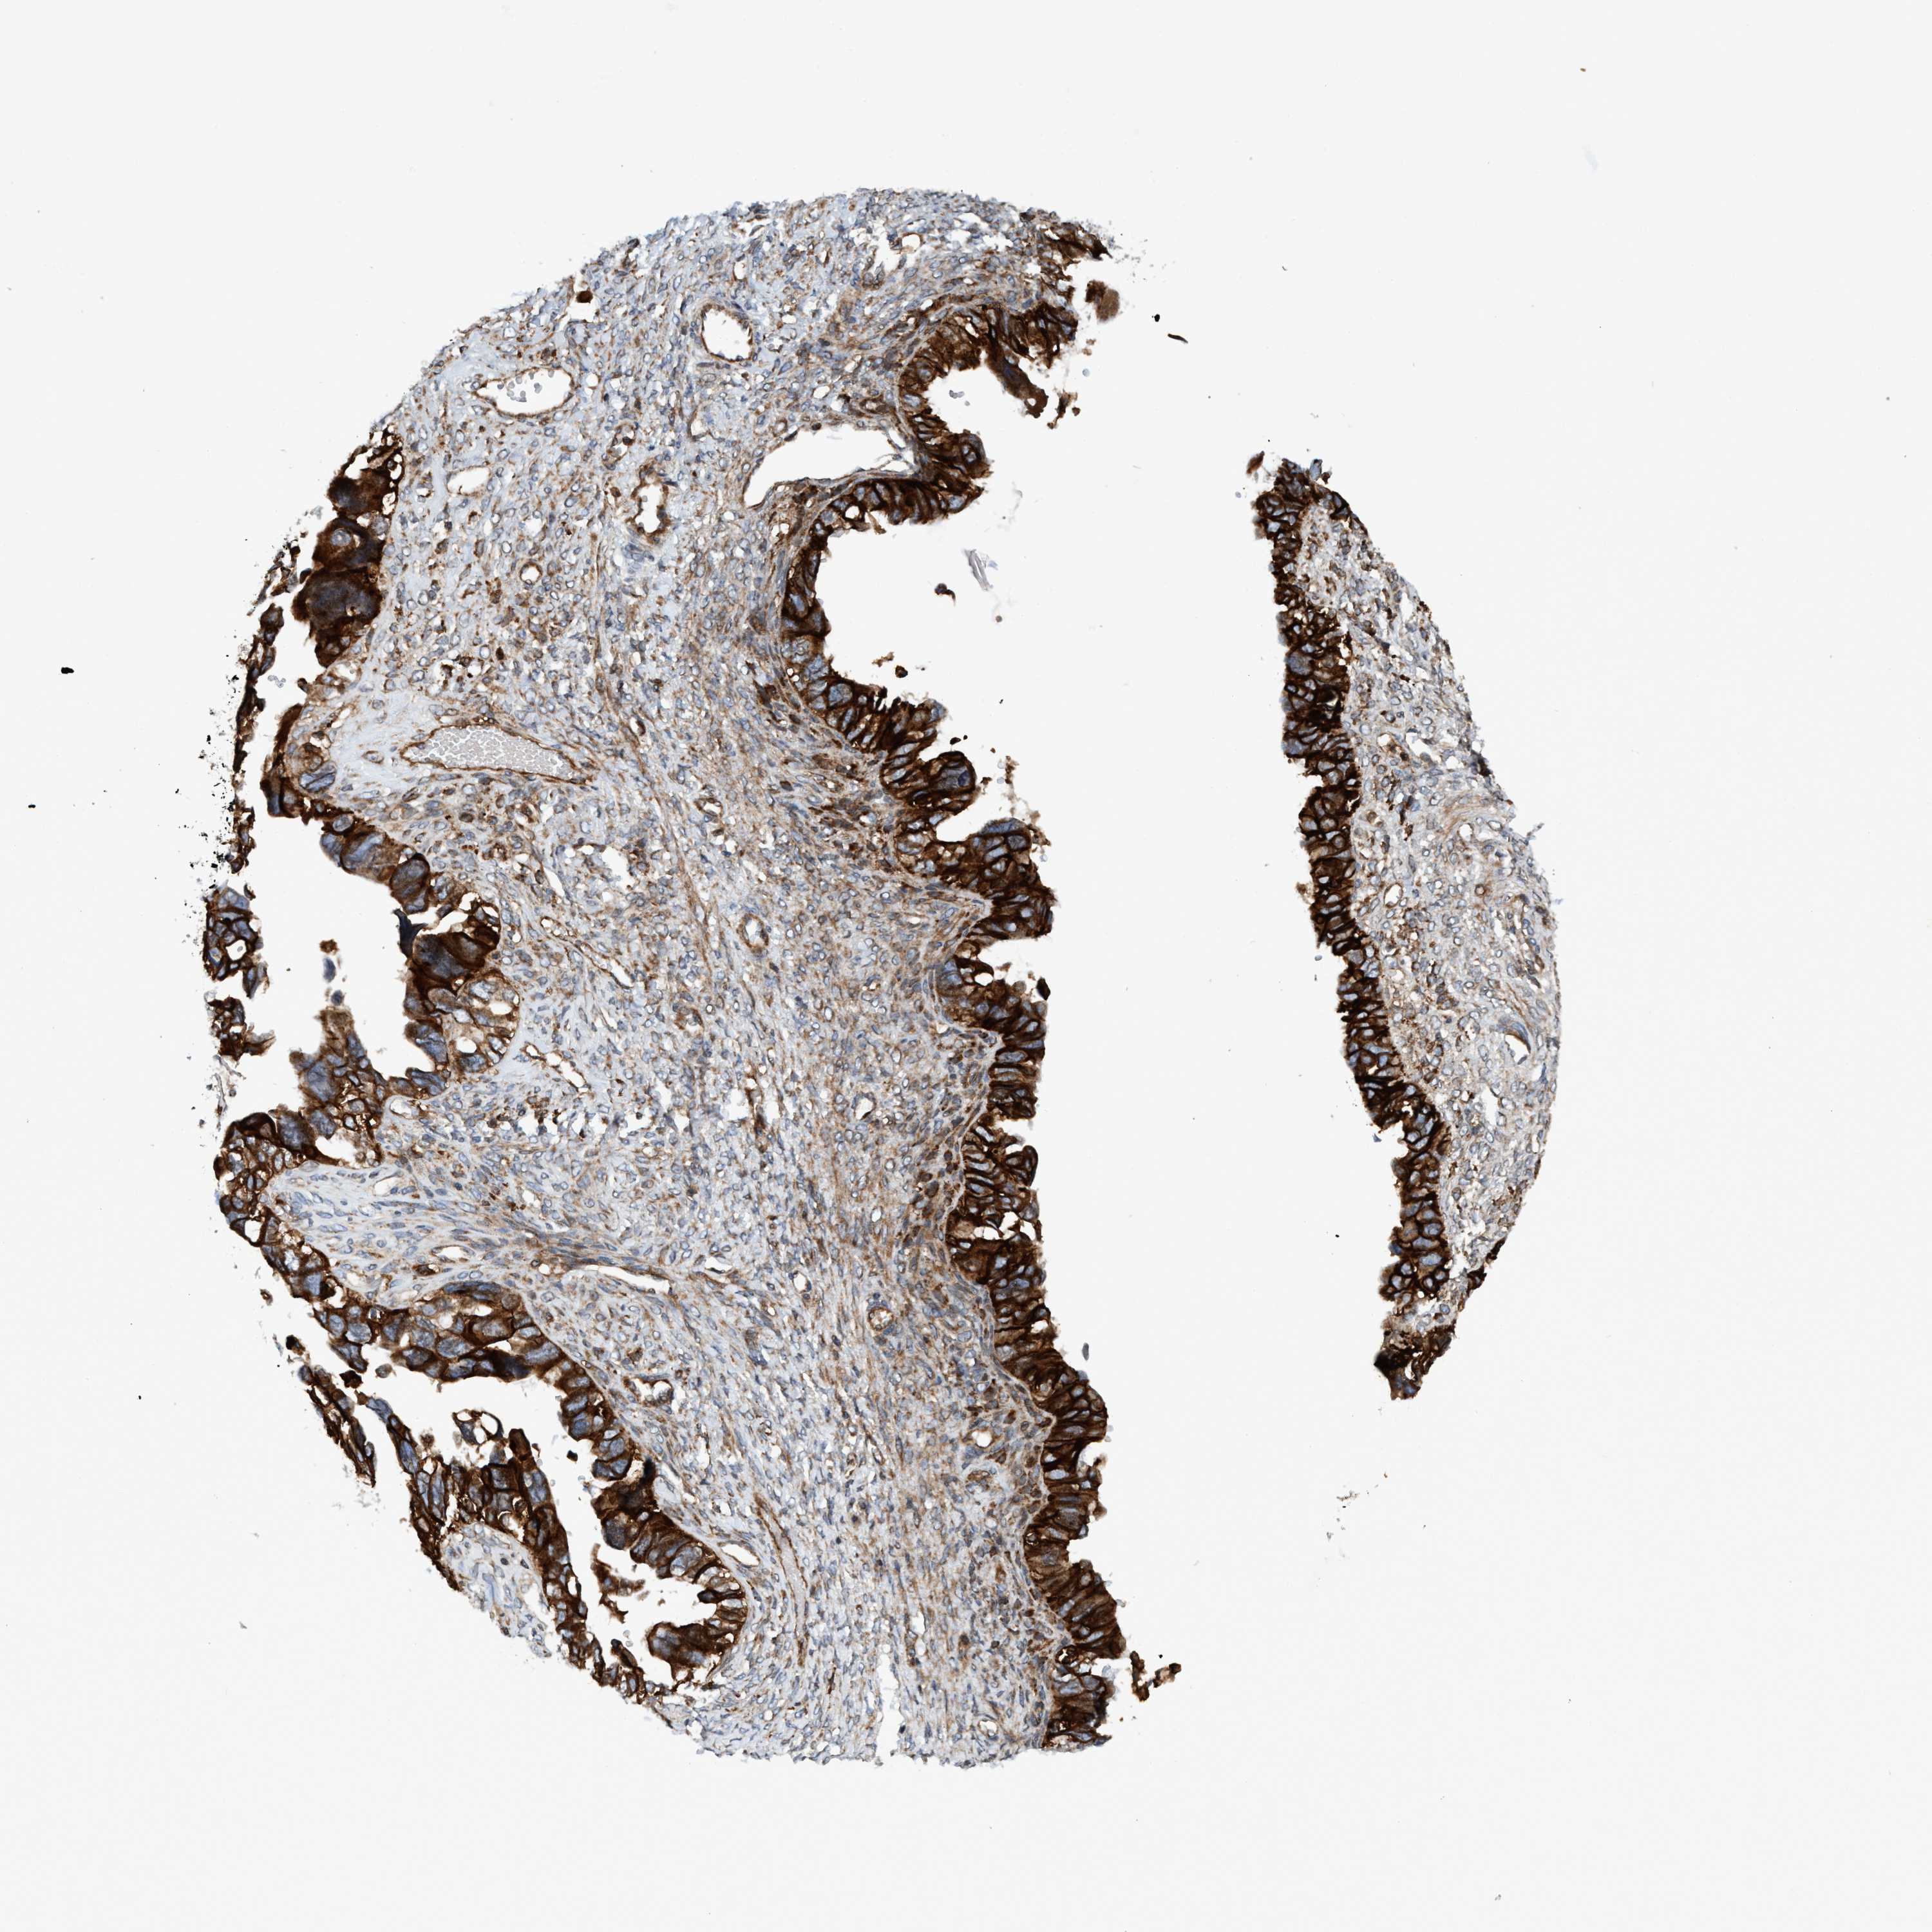

OVARIAN CANCER - Protein expressioni

A mouse-over function shows sample information and annotation data. Click on an image to view it in a full screen mode. Samples can be filtered based on level of antibody staining by selecting one or several of the following categories: high, medium, low and not detected. The assay and annotation is described here.

Note that samples used for immunohistochemistry by the Human Protein Atlas do not correspond to samples in the TCGA dataset.

Antibody stainingi

Antibody staining in the annotated cell types in the current human tissue is reported as not detected, low, medium, or high, based on conventional immunohistochemistry profiling in selected tissues. This score is based on the combination of the staining intensity and fraction of stained cells.

Each image is clickable and will lead to virtual microscopy that enables deeper exploration of all samples and also displays staining intensity scores, fraction scores and subcellular localization as well as patient and tissue information for each sample.

Antibody HPA021451

Antibody CAB017490

Cystadenocarcinoma, serous, NOS

Carcinoma, endometroid

Cystadenocarcinoma, mucinous, NOS

Carcinoma, NOS